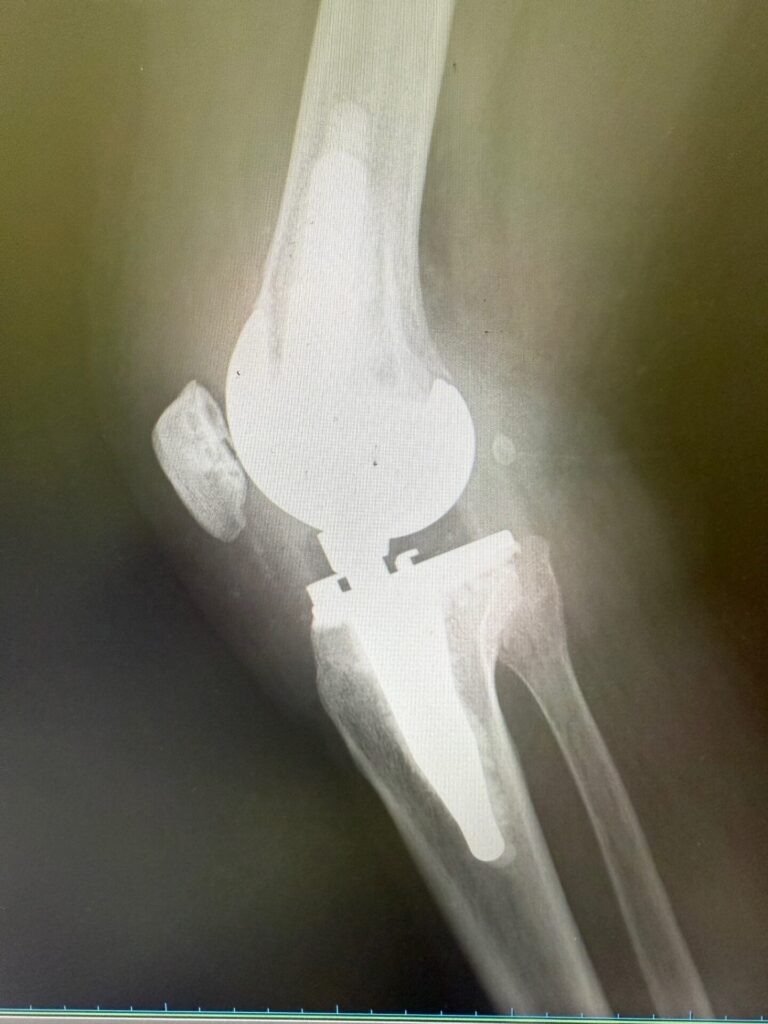

メディカルチェックで、レントゲン上特にヘルニア等の問題はないが、正面像で軽度側弯症、側面像でのアライメント不良判明。

人工膝関節術後の自費リハビリによって更なる日常パフォーマンス向上を希望され会員となられた方。

健康保険での術後回復期リハビリも終えられたが、更なる日常パフォーマンス向上を希望。

メディカルチェックの結果、術後の合併症のためか(?)、腓骨神経麻痺による足関節背屈力低下と腓骨神経領域の軽い痺れ感を認め、日常パフォーマンス向上を妨げる一因となっている可能性も考えられた。クリニックで経過観察しながらフィットネス開始。